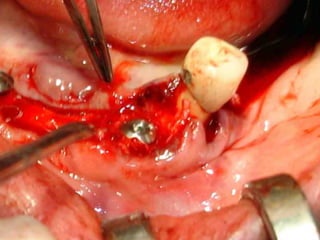

Segundo tiempo quirúrgico para aplicar la estructura.

Estructura en íntimo contacto con la superficie ósea, quedando los postes

fuera de la fibromucosa gingival..

Sutura de colgajos que cubren la estructura, dejando los postes bien visibles.

Colocación de la prótesis dentaria.